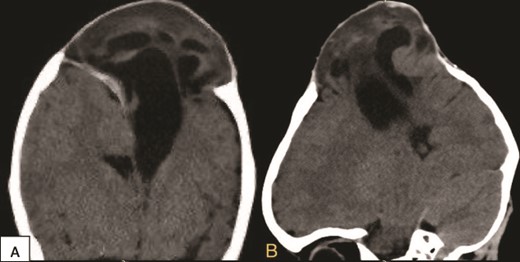

Furthermore, a decision to perform a cranioplasty was made immediately. In the operation the previous bicoronal flap was reopened, isolating the encephalocele. It was found a newly formed tough ring of bone encircling the base of the encephalocele, with the edges of this bone intruding into the brain tissue with significant adhesions, indicating abnormal bone growth around the affected area. Carefully, the newly formed bone was removed to reach the healthy bone of the skull. A temporary EVD was used alongside mannitol administration and hyperventilation to reduce the CSF. The sac was pushed inside and subsequently, a decision for 3D cranial mesh (Fig. 3) closure was made to cover the defect in the cranium for finally close the incision normally. Postoperative CT scan was done (Fig. 4), demonstrating that the brain went inside with no postoperative complications. There was notable improvement in the motor functions of the right limbs and absence of spasticity in the right upper limb. Two days later the patient was discharged home, active and able to walk without assistance.

Intraoperative view of the case. (A) Showing the ossification and adhesion of the bone to the brain tissue. (B) Showing the cutting technique used to separate the bone. (C) Showing the brain tissue separated from the bone and free. (D) Showing the cranial mesh inserted to cover the cranial defect and protect the brain tissue.